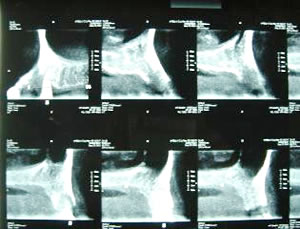

頭蓋全体のCTでインプラント埋入可能な部位を検討します

下顎のCTで骨の幅と埋入部位を決定します

デンタルCT 3DX装置ではより精密な検査が可能になりました

デンタルCTで上顎洞までの骨の厚みが正確に分かり安全に手術が行えます